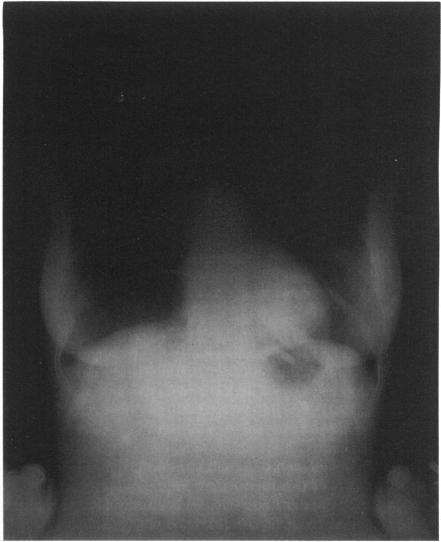

Pulmonary tuberculosis: evolution of modern therapy.

Bull N Y Acad Med. 1973 Mar;49(3):163-96.